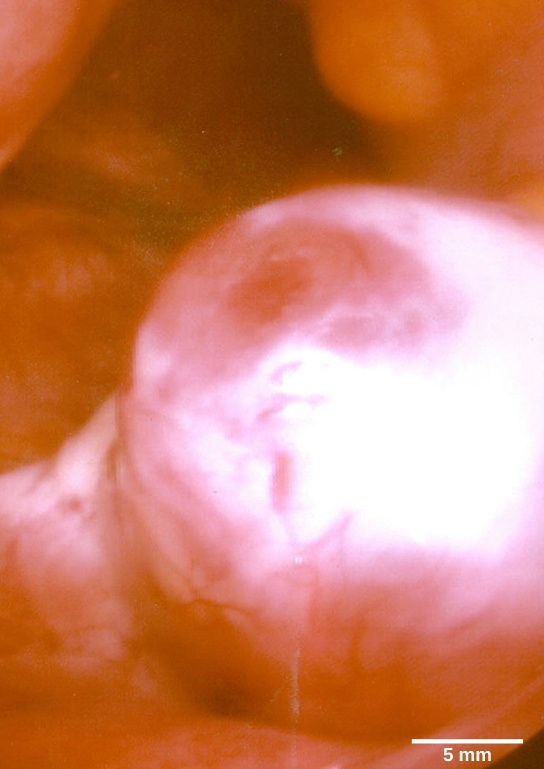

Just prior to the middle of the cycle (approximately day 14), the high level of estrogen causes FSH and especially LH to rise rapidly, then fall. The spike in LH causes ovulation: the most mature follicle, like that shown in the figure below, ruptures and releases its egg. The follicles that did not rupture degenerate and their eggs are lost. The level of estrogen decreases when the extra follicles degenerate.

Micrograph shows a spherical egg growing on the surface of a tissue.

This mature egg follicle may rupture and release an egg. (credit: scale-bar data from Matt Russell)